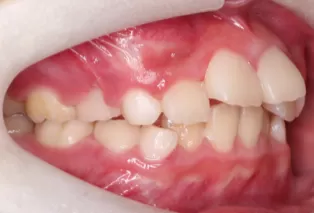

Patient: Female, 11 years old

Conditions: Deep overjet, upper anterior teeth protrusion

Treatment Device: K3

Intraoral photos